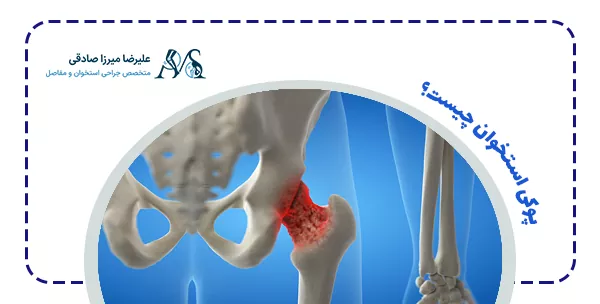

پوکی استخوان چیست؟

پوکی استخوان بیماریای است که در آن بافت استخوانی به مرور نازک و شکننده میشود و توانایی تحمل فشارهای معمول را از دست میدهد. در نتیجه، فرد مستعد شکستگیهای مکرر میشود. این بیماری اغلب بدون علامت خاصی پیشرفت میکند و به همین دلیل به آن “بیماری خاموش” نیز میگویند.